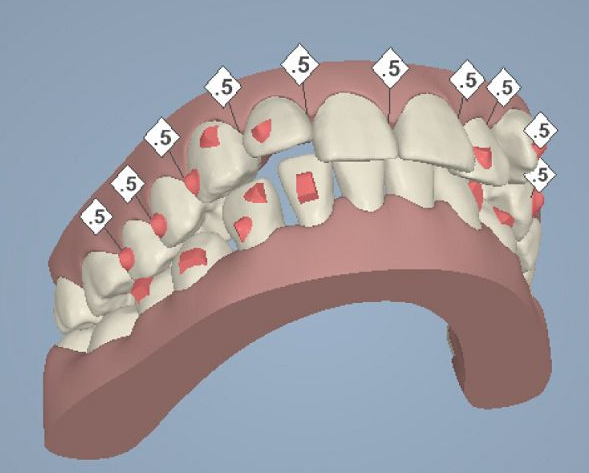

但是有了骨釘植入,就可以解決前者調(diào)節(jié)方案的煩惱,可以根據(jù)不同的調(diào)節(jié)方案,不同的調(diào)節(jié)需求,在口腔中相應(yīng)的位置植入骨釘形成口腔中的一個受力點(diǎn),同時利用正畸器,橡皮筋相互拉力的作用下,更好的幫助醫(yī)生更好的控制牙齒的移動,做到"該移動的牙移動,不該動的牙不動"從達(dá)到佳的調(diào)節(jié)果。

小骨釘雖然作用很大,但是并不是所有的牙齒矯正都需要植入骨釘,只有針對復(fù)雜的正畸類型才需要植入骨釘。

那么什么樣的牙齒情況需要植入骨釘呢?1.牙齒呈現(xiàn)深覆合或者咬合過深的患者。

2.常見的牙齒反頜現(xiàn)象,俗稱兜齒或者地包天的患者

3.有牙周病、牙齒損傷嚴(yán)重沒有足夠數(shù)量的支抗牙

4.正畸前,牙縫過大,或是拔過牙,可利用植入骨釘來加強(qiáng)牙齒后退力量